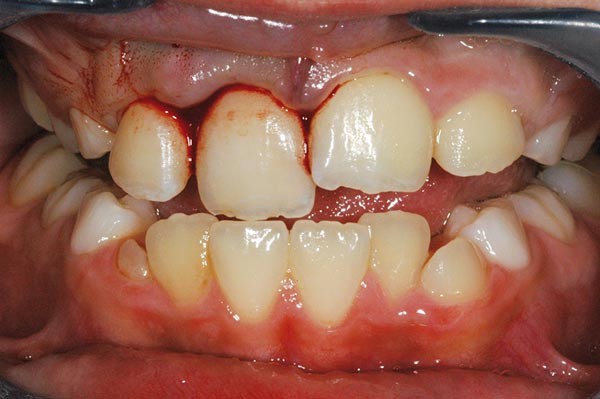

À l’examen clinique, le fragment coronaire peut être mobile, déplacé(fig. 1 et 2) et présenter une dyschromie transitoire de la couronne. Dès lors, un certain nombre de tests complémentaires s’impose.

La mobilité. Le degré de mobilité dépend de la situation du trait de fracture [4]. Plus la situation est coronaire, plus la mobilité est importante. Lorsque le trait de fracture est situé au tiers apical, la mobilité peut être physiologique et souvent, dans ce cas, la fracture radiculaire est mise en évidence lors de l’examen radiographique.